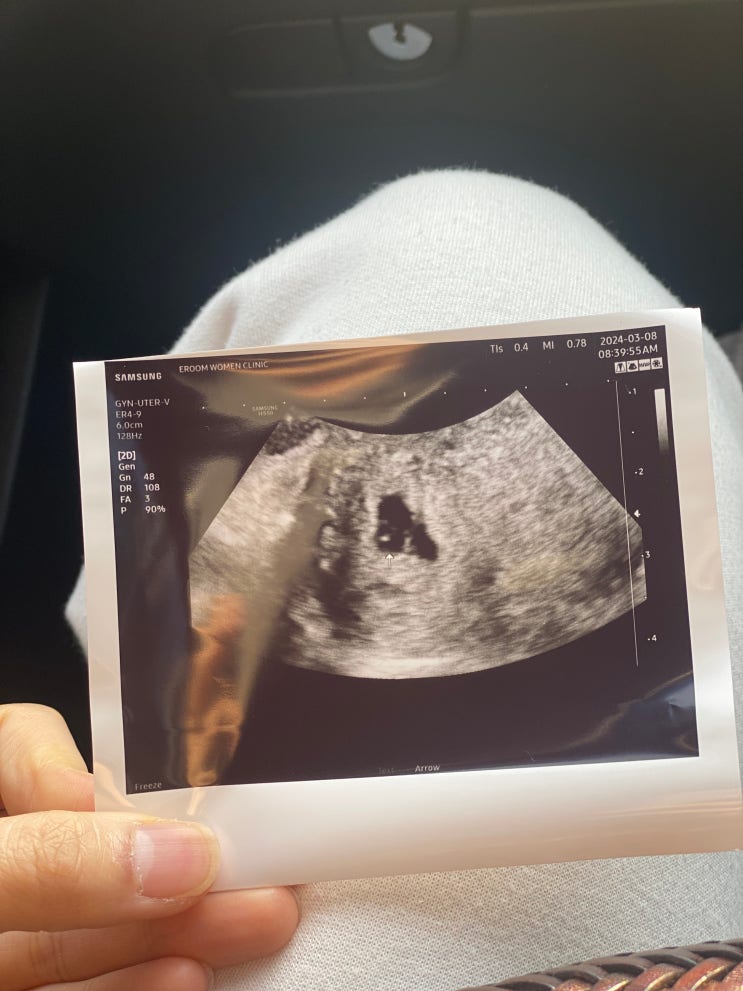

난임일기 동결1차 #7 - 5일배양포배기 이식 19일차. 입터짐, 아기집확인, 난황확인, 파이널임테기, 스마일더블체크.

3/8 19일차 5주2일 아기집.난황확인 드디어 아기집 보러가는 날 사실 1차,2차 피검때 보다 더 가슴 졸였던 ...